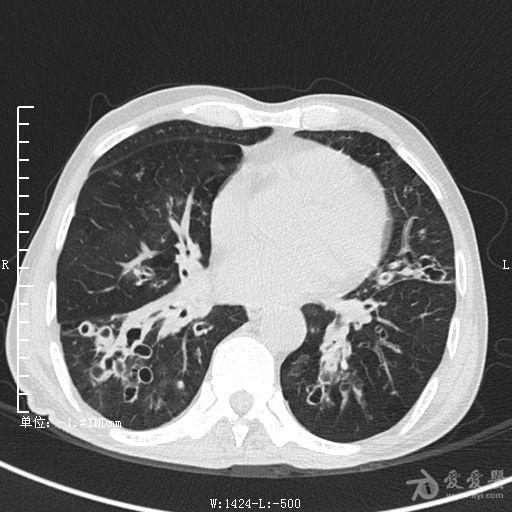

典型支气管扩张及肺水肿CT片

典型支气管扩张肺水肿